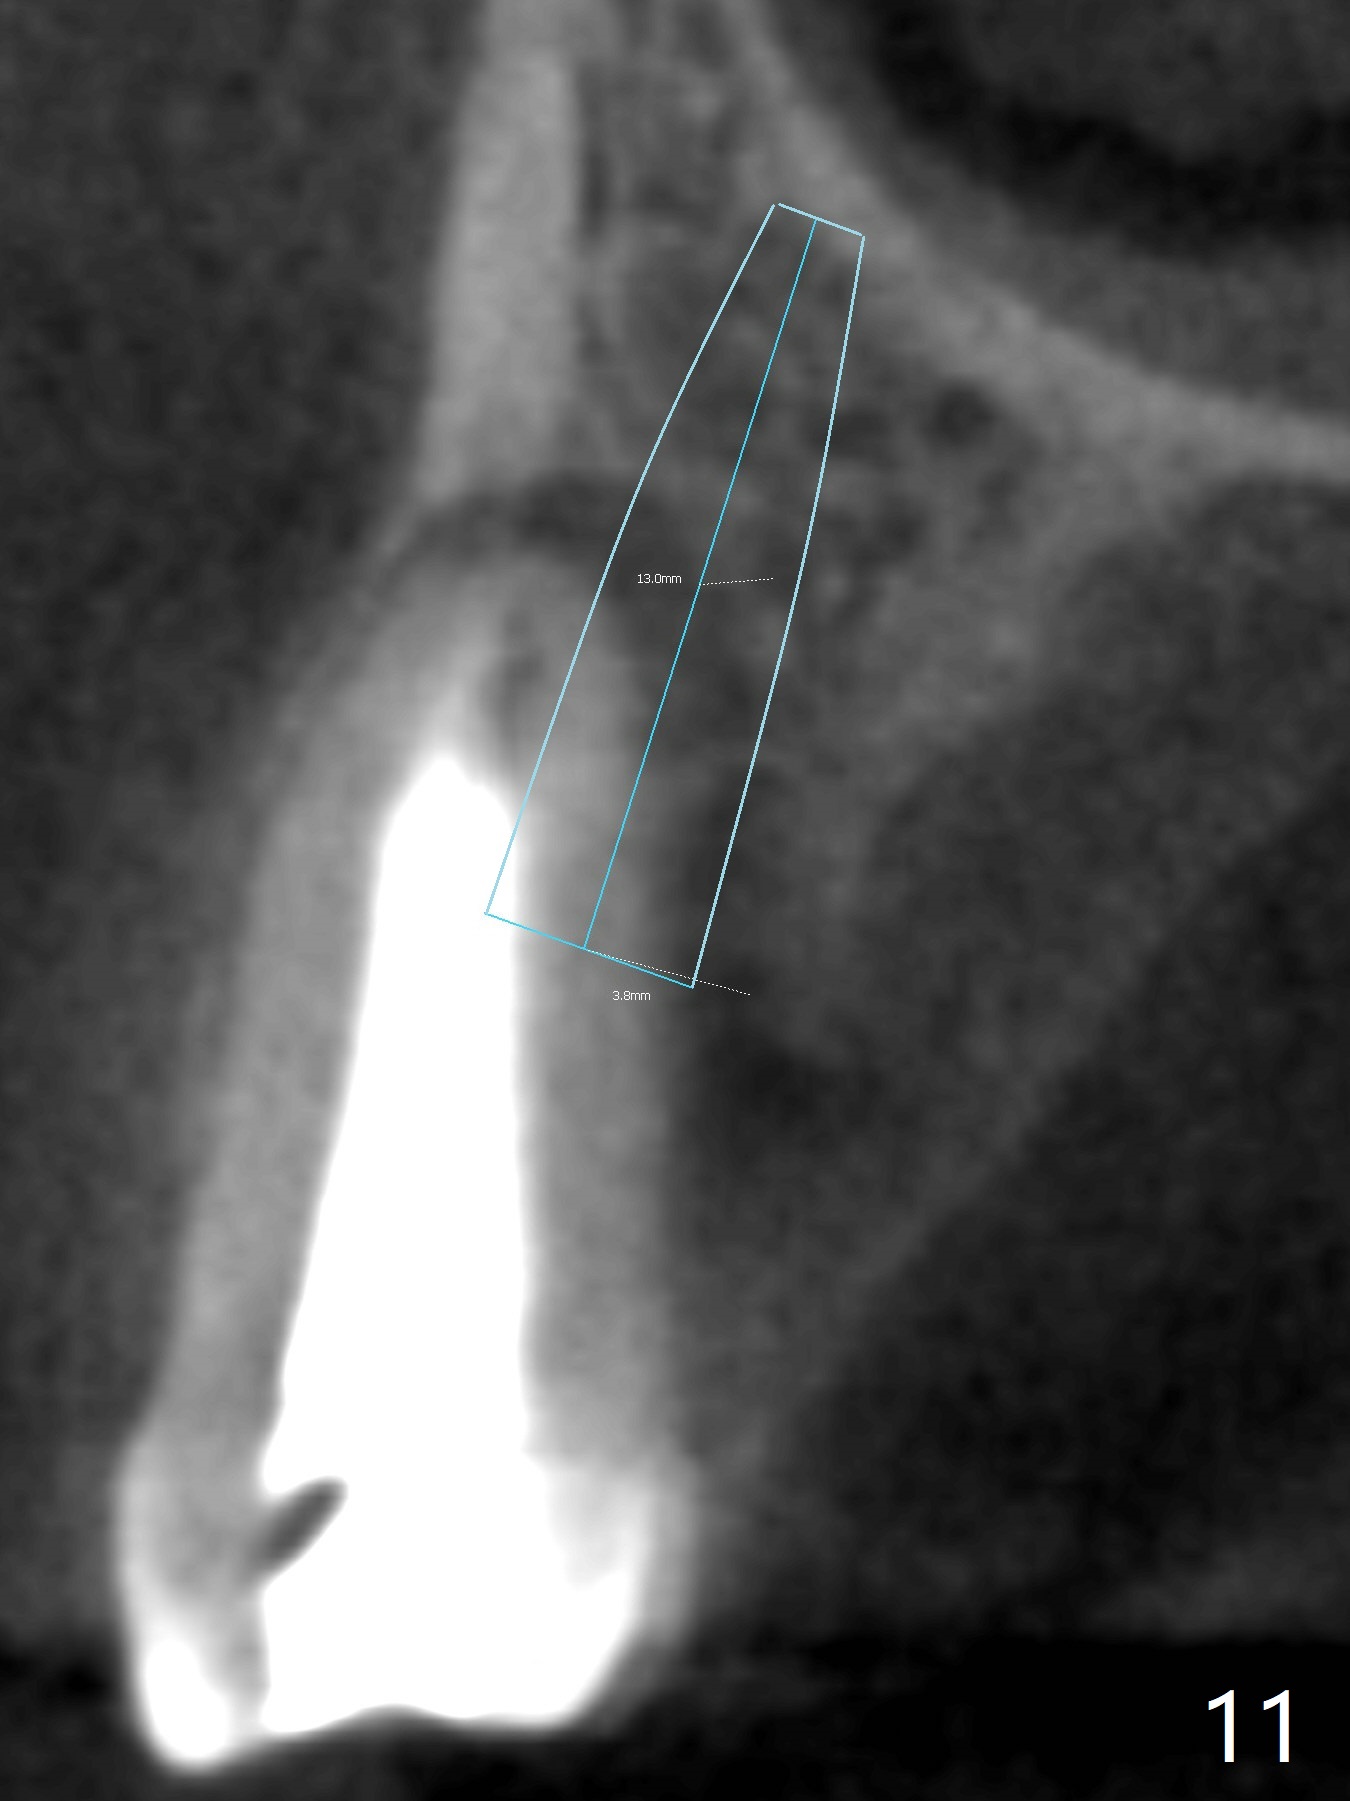

In fact there is a small buccal fistula, which is communicated with the underlying implant threads. Although preop CT shows that the buccal crest is lower than the palatal (3.8x13 mm, Fig.10 P) one, intraop finding of missing buccal plate should dictate a shorter implant (Fig.11) or onlay graft to avoid periimplantitis. Regeneration of the bone plate is limited. Later the fistula disappears with formation of a concavity (Fig.13). There is no symptom. Is bone graft necessary with a remote incision? 3-D images of CT taken 1 year 5 months post cementation show possible mesiobuccal and distopalatal bony defects (Fig.13-16). It is possible that bone graft was placed enough palatal (Fig.16). DO composite at #3 is redo satisfactorily (Fig.17 *).